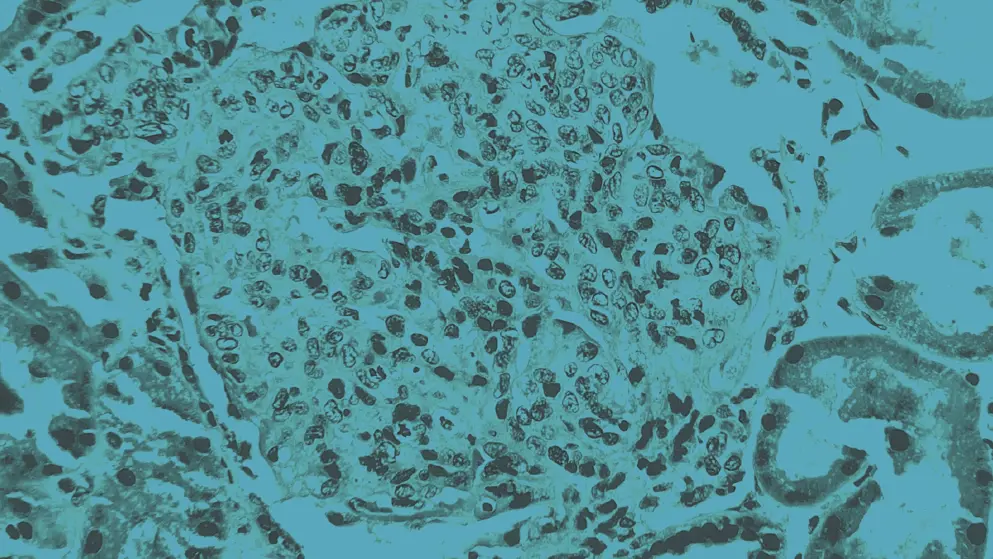

Diagnosing lupus is complex due to its diverse and evolving clinical presentation. No single test confirms SLE. Diagnostic tests include full blood count, erythrocyte sedimentation rate, renal and liver function tests, urinalysis, and, when indicated, imaging or biopsy.